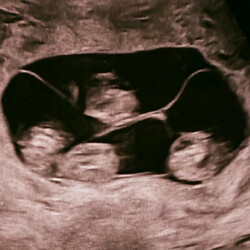

Однояйцевые четверняшки родились в роддоме № 17 в Санкт-Петербурге. Их появление на свет – это один случай на 15,5 миллиона родов, сообщили в медучреждении.

«Чудо в четвертой степени: в нашем роддоме родилась четверня! (...) На сроке 32 недели на свет появились четыре очаровательные сестренки. По расчетной статистике монохориальная - "однояйцевая" четверня – один случай на 15,5 миллиона родов. В стране не описано таких уникальных родов», – говорится в сообщении роддома в соцсети «ВКонтакте».

По информации РИА Новости, вес новорожденных девочек составляет от 1,36 до 1,64 килограмма, рост – от 37 до 41 сантиметра. По оценке специалистов родильного дома, это прекрасные показатели для рождения на таком сроке.

Всего в мире насчитывается около 15 идентичных четверняшек, причем 10 из них — девочки.